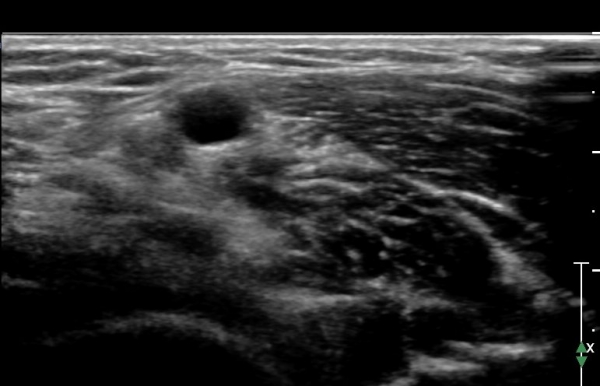

ÃÊÀ½ÆÄ °Ë»ç : ȸ³»±Ù ±ÙÀ§ºÎ¿¡¼­ Á¤Á߽Űæ Ⱦ´Ü¸é°Å»ç¿¡¼­ ƯÀÌ ¼Ò°ßÀ» º¸ÀÌÁö ¾ÊÀ¸³ª(»çÁø 1) ȸ³»±Ù ¿ä°ñµÎ ±â½ÃºÎ

¿¡¼­  Á¤Á߽ŰæÀÇ ±¹°íÀû ¾Ð¹Ú ¹× ÆíÆòÈ­°¡ °üÂûµÊ(»çÁø 2). ÀÌ·± º¯È­´Â °ÇÃø(»çÁø 5)°ú ºñ±³Çϸé

¶Ñ·ÇÇÔ.